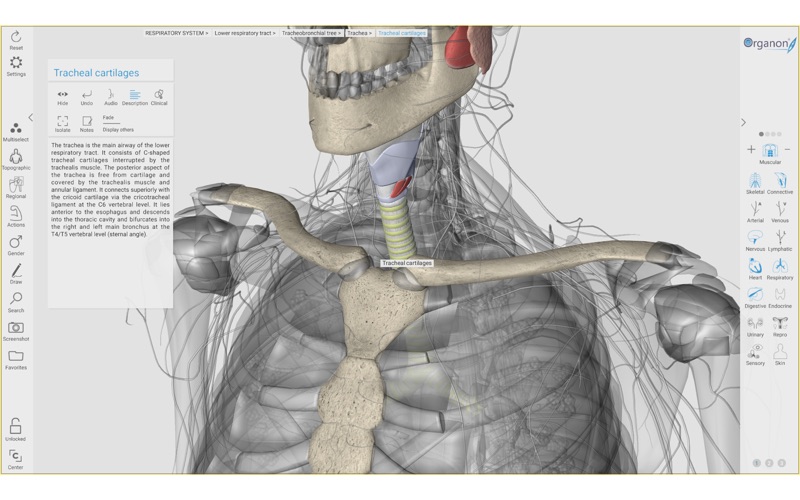

1. The latest update also brings you more stunning features, such as multiple workspaces, live anatomy annotation tool during navigation, unique topographic anatomy layout, help tutorials, and visualization of anatomy with incredible detail.

2. 3D Organon Anatomy is an interactive anatomical atlas featuring all 15 human body systems.

6. It features all body systems: Skeletal, Connective, Muscular, Arterial, Venous, Nervous, Lymphatic, Heart, Respiratory, Digestive, Endocrine, Urinary, Reproductive, Sensory organs, and Integumentary (skin).

10. 3D Organon unfolds life-like high resolution 3D models covering every aspect of the human body.